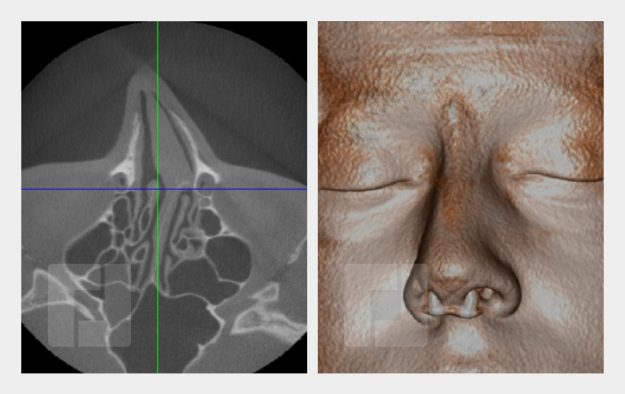

Beispiele

Durch Öffnen der Bildergalerie haben Sie die Möglichkeit selber durch die Beispiele zu navigieren.